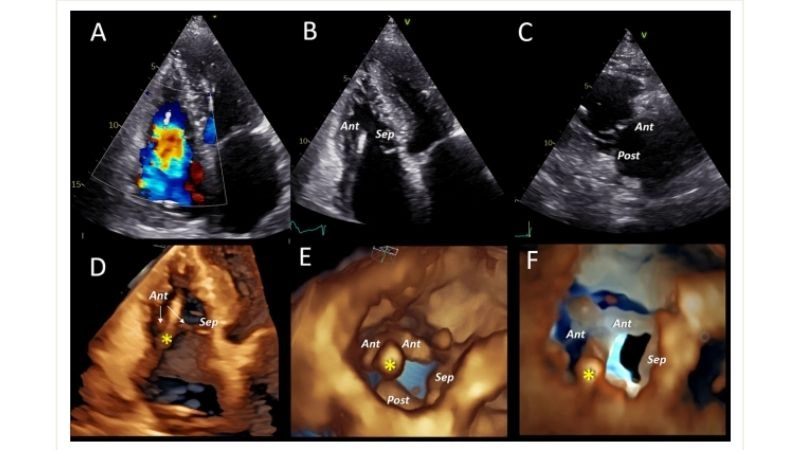

Images visual examples of Tricuspid Regurgitation (Insufficiency)

Visual examples often show an enlarged right atrium and ventricle, with abnormal blood flow patterns detected through echocardiography. These images help illustrate the mechanical dysfunction that contributes to the disease.

Tricuspid Regurgitation Diagnosis confirmed with echocardiogram

Tricuspid Regurgitation Echo helps measure severity